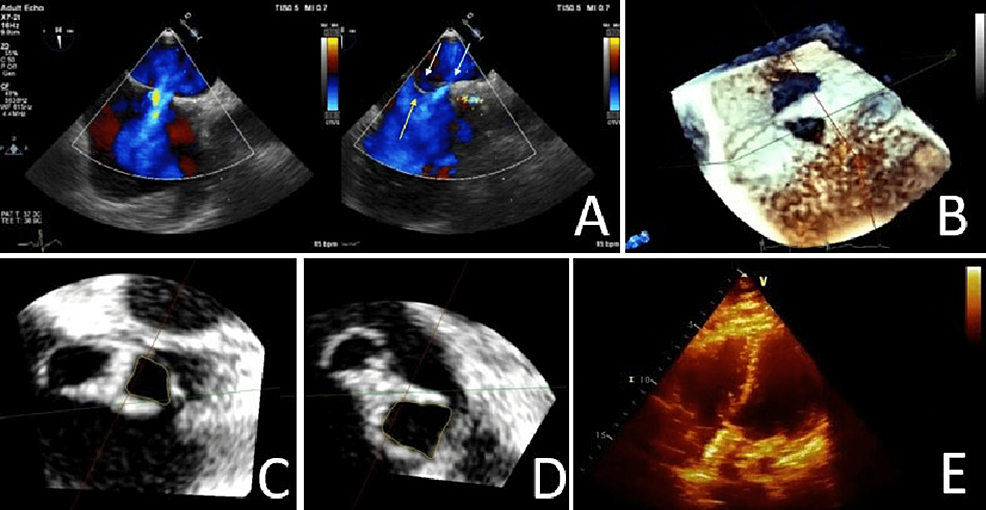

Cureus ThreeDimensional Cardiac Imaging A Necessity to the What Is Swiss Cheese Defect — multiple muscular vsds, also known as swiss cheese ventricular septum, are significantly more complex. When used in conjunction with traditional patch repair, tar minimizes the amount of patch material requiring, thereby reducing septal dysfunction. “swiss cheese” defects are defined as the presence of uncountable vsds in the trabecular septum. — for patients with multiple ventricular septal. What Is Swiss Cheese Defect.